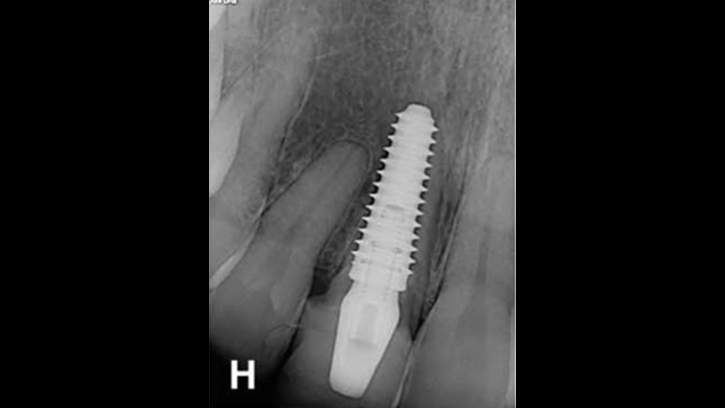

Clinical case: Immediate post-extraction insertion of implant & immediate loading

- Courtesy of Prof. Giuseppe Luongo, Italy -

AnyRidge, immediate loading, single implant, multicenter study, maxillary anterior, Prof. Giuseppe Luongo, single replacement

AnyRidge implant system

Immediate functional loading of single implants: a multicenter study with 4 years of follow-up

/J Dent Res Dent Clin Dent Prospect 2018; 12(1):26-37 | doi: 10.15171/joddd.2018.005

https://www.ncbi.nlm.nih.gov/pubmed/29732018